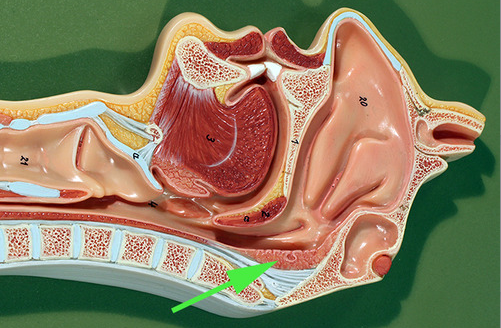

The structure indicated by the green arrow is the

pharyngeal tonsil

The structure marked by the green arrow is a palatine tonsil

The green arrow is indicating a tonsilar crypt